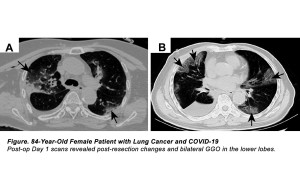

Grappling with Coronavirus (SARS-CoV-2)